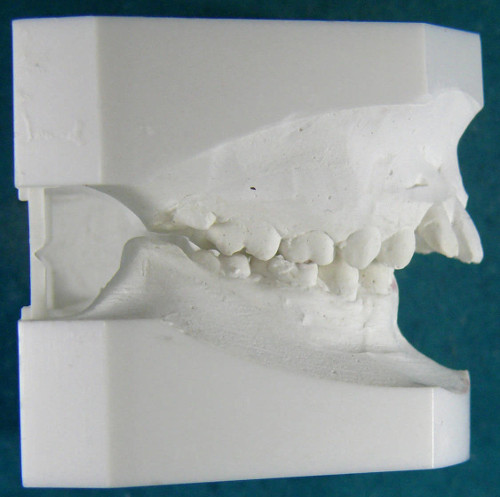

Abb. 1: Gesockeltes Gipsmodell, vor der Behandlung [Dr. Nessler]

Zu Beginn der diagnostischen Schritte nehmen wir Abdrücke von den Ober- und Unterkiefern unserer Patienten. Diese dienen der Herstellung von gesockelten Gipsmodellen, die uns erste Anhaltspunkte zu Zahn- und Kieferfehlstellungen liefern können. Anhand dieser Modelle können wir Ihnen und Ihren Kindern auch sehr gut den Fortschritt der Behandlung aufgrund der sichtbaren Veränderungen der Zahnreihen und Kieferstellung verdeutlichen.